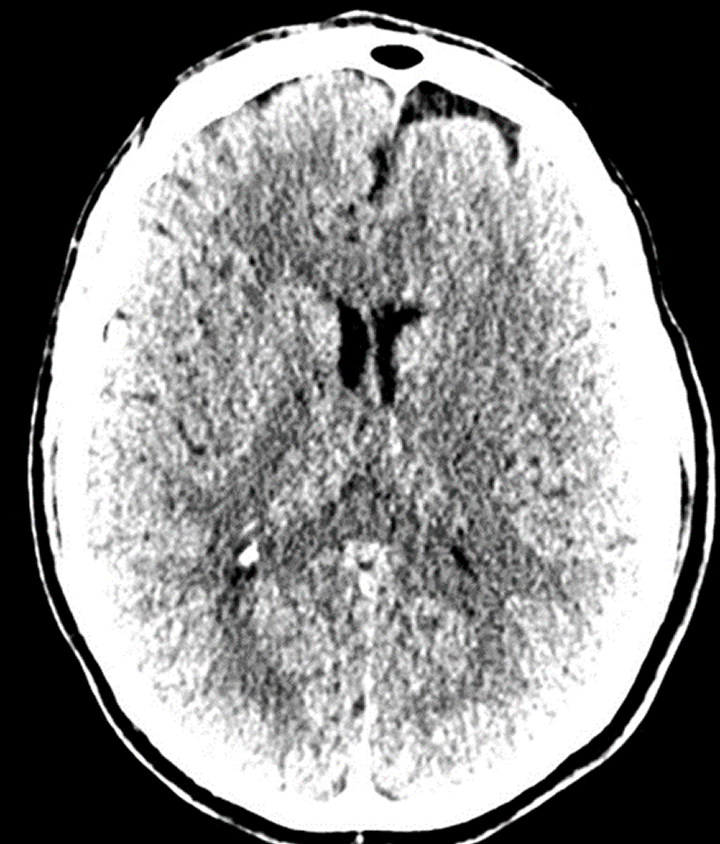

radiology

Vessel and Brain tumor segmentation

datascientists before

Before: "fuzzy" head CT

datascientists after

After: detailed images

Our V Star computer scientists wrote a module for 3D-Slicer allowing careful alignment and summation from 8 prior CT scans obtained over a course of several years. This improved image contrast resolution without loss of spatial resolution